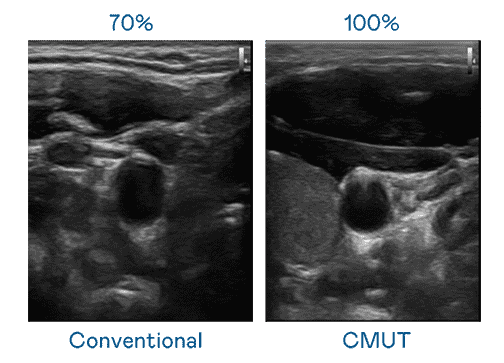

CMUT 技术是一种用电容式微机电元件来产生超音波讯号的技术。。。。与传统 PZT 压电式技术相比,,,,CMUT 频宽增加 30%,,更宽频的超音波讯号让影像解析度大幅提升,,,是实现高影像品质医疗超音波扫描、、促进精准医疗发展的关键技术。。

大频宽带来超清晰影像

超音波影像的解析度高低,,,首先取决于探头能发出的讯号频宽。。NG大舞台 CMUT 可提供高清晰的超音波讯号,,提供高频宽、、、高灵敏度、、、影像纹理细节更高的超音波影像,,,协助医护人员缩短影像判读时间及利用精准的医疗影像进行诊断。。。